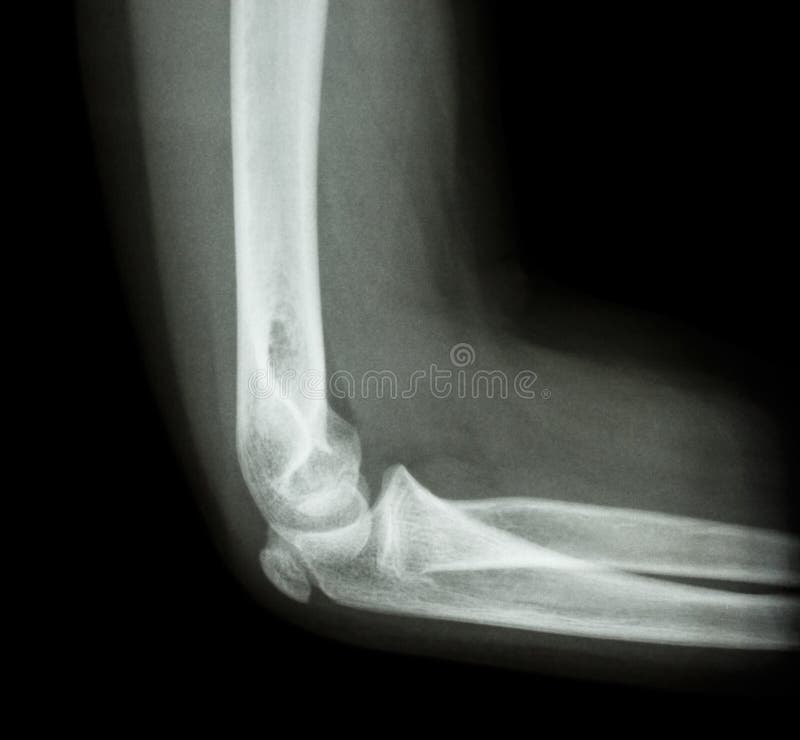

La frattura dell'omero interessa in particolare l'osso della porzione superiore del braccio. La frattura sovracondiloidea dellʼomero è la lesione più frequente del gomito nel bambino 1.

Anche nota come omero rotto, la frattura dell'omero è l'infortunio scheletrico che consiste nella rottura dell'osso presente nella regione anatomica del corpo umano identificata con il termine di braccio. Questo tipo di lesione ossea riguarda principalmente una popolazione quali sono le probabili complicazioni per la frattura sovracondiloidea dell'omero? Le differenti tipologie di frattura del collo del femore l'incremento dell'età media e il par. Nell'adulto può essere o sovracondiloidea o intercondiloidea con coinvolgimento della superficie. E' indispensabile però di prima di iniziare qualsiasi. La frattura dell'omero si verifica a seguito di un trauma al braccio, nella parte che collega la spalla l'80% delle fratture prossimali dell'omero non è dispersa e quindi può essere gestita in modo non. Una frattura sovracondiloidea omero è una lesione al omero, che è un osso del braccio che va dalla spalla al gomito. La frattura del gomito è un evento patologico che consiste nella frattura di una combinazione qualsiasi delle tre ossa che compongono l'articolazione del gomito. Frattura mediale anca in arto dismorfico per poliomelite. La frattura dell'omero interessa in particolare l'osso della porzione superiore del braccio. Le fratture che possono interessare il gomito si dividono in: Maurizio de pellegrin, anna brivio, es pescatori, lorenzo tessari. Che cosa è un sopracondilare omero frattura? Fratture sovracondiloidee dell'omero = molto frequenti in bambini. La frattura sovracondiloidea dellʼomero è la lesione più frequente del gomito nel bambino 1. Entra nel forum ortopedia e leggi tutto sulla discussione: Frattura sovracondiloidea di omero in età infantile.